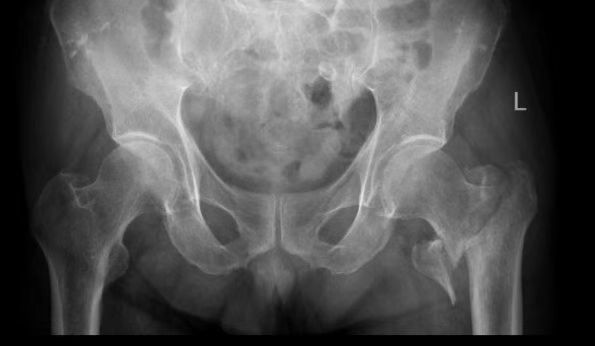

患者张爷爷已逾九旬,基础疾病错综复杂:前列腺癌病史3年、高血压20年、糖尿病30年,10天前因脑梗死导致左侧肢体活动不便。然而近日,厄运再次降临,他在家如厕时不慎跌倒,造成“左侧股骨转子间粉碎型骨折”,被紧急送至该院。

入院时,老人情况十分危急:除骨折外,还存在Ⅰ型呼吸衰竭、慢性支气管炎急性加重、低钠血症及贫血等疾病。入院后其呼吸功能进一步恶化,随即被转入ICU,进行气管插管、呼吸机辅助呼吸。经过ICU团队5天昼夜不停的全力救治,张爷爷的呼吸功能终于显著改善,成功拔管,脱离了生命危险。